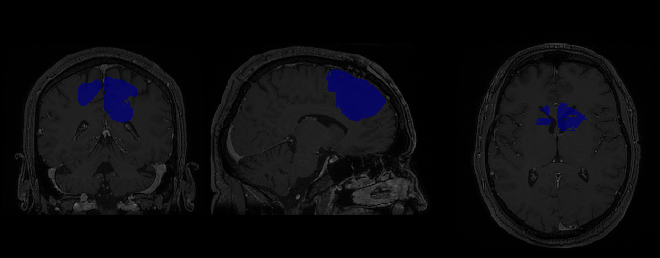

Each pre-operative and post-operative scan is a T1-weighted MRI accompanied by B-mode (Ultrasound) images. The images of the BITE database are split into four groups based on the specific analysis performed by the neurosurgeons. Our analysis is centred on group number three which includes 14 MR images taken before and after the patient’s surgery. The dataset is stored in Medical Imaging NetCDF (MINC) format the standard format at the Montreal Neurological Institute for image processing. MINC data can contain signed and unsigned integer, float and complex data types accompanied by a prepackaged extensible binary format header containing all relevant information regarding the corresponding patient, tumor region and cancer type. Group three of the BITE dataset contains images related to 14 patients all of which were identified to have brain cancer, see Figure. 2 above. Unfortunately, no pre-operative scan was performed on patient number 13 of the dataset meaning that no manual binary map of the ROI was manually extracted as the patient’s pre-operative scan does not exist, hence, patient 13 will be excluded from the future analysis that this paper will propose.

To extract meaningful information from this dataset we primarily used the programming language python333van Rossum, G., 1990. Python. www.python.org coupled with neuroimaging libraries such as Nibabel444Markiewicz, C., 2006. Nibabel. www.nipy.org/nibabel NiPy. and Nilearn5552019. Nilearn. https://nilearn.github.io NiPy. which allowed for easy manipulation of the images. Nibabel was used to load the images in as Nibabel objects which could then be easily converted into numpy arrays to manipulate the images affine matrix. Nilearn a popular python neuroimaging library comes pre-packaged with plots suitable for the visualisation of MR images. Figure. 2 shows a basic anatomical plot to show the three image perspective planes of a specific MR image. This plot can be altered to visualise different slices of each image plane by manipulating the coordinates of the MR image. By manipulating the coordinates of the image, plots can be designed around the images shape where functions intake a basic slice number as a parameter and increment through the slices of the image displaying each slice as the function increments through the numpy array.

The ground truth accompanying this dataset has several issues that can impact the segmentation performance an algorithm may propose. Most notably, the binary mask of each patient varies in image resolution to the patient’s pre-operative scan. The resolution of each binary mask does not match the resolution of each pre or post-operative image. Why does this difference in resolution matter? U-Net intakes an MR two-dimensional image and outputs a segmentation of the ROI supplied to the network. The ROI and the output of the network must be the same resolution of the input image. With the difference in resolution, we are unable to utilize either of these networks until the resolution of the tumor masks is resolved. The difference in image resolution is due to the images being stored in MINC format. This format enables analysts to store cropped regions without losing any coordinate information, making it possible to overlay the full pre-operative MR image with its corresponding small tumor mask without suffering any error in alignment. To overlay a tumor mask with a pre-operative MRI scan we can use one of Nilearns built-in plotting functions to create an ROI plot.

Refer to caption

Figure 3: ROI overlay plot, showing patient 2’s binary mask overlaid onto their pre-operative scan showing the size, shape and location of their tumor.

Figure. 3 represents an ROI plot, where the tumor mask has been overlaid onto the corresponding pre-operative scan. This figure provides us with crucial information regarding the size, shape and location of the patient’s tumor. Using Nilearn we can resample the mask to a target dimension. A useful feature which expands our original binary mask to match the image dimensions of each pre-operative scan. The re-sampled mask now meets its corresponding pre-operative mask in terms of height and width, however, this function also reshapes the MINC files slices. As patient 1 has 29 slices compared to 180 the function will add the extra slices to the binary mask so that each scan can be equal. Thus, with this new re-sampled dataset we can begin to explore tumor segmentation using relevant algorithms. Most notably, U-Net works with two-dimensional data. To reformat the MINC data we can extract these 180 slices as two-dimensional images, where each slice represents one image. These slices are then classified as the three perspective planes of the brain, ie., coronal, sagittal, and transversal. Repeating this procedure on 13 patients will create a large dataset for our analysis.